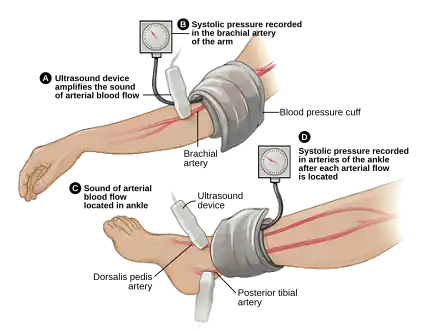

A vascular surgeon may diagnose PAD using a combination of history, physical exam and medical imaging. Medical imaging may include ankle-brachial index, doppler ultrasonography and computed tomography angiography, among others. Treatments are individualized and may include medical therapy, endovascular intervention or open surgical options including angioplasty, stenting, atherectomy, endarterectomy and vascular bypass, among others.

ABI testing is used by vascular surgeons in the diagnosis of PAD. The blood pressure in the arm and leg are compared as a ratio.

ABI testing is used by vascular surgeons in the diagnosis of PAD. The blood pressure in the arm and leg are compared as a ratio. -